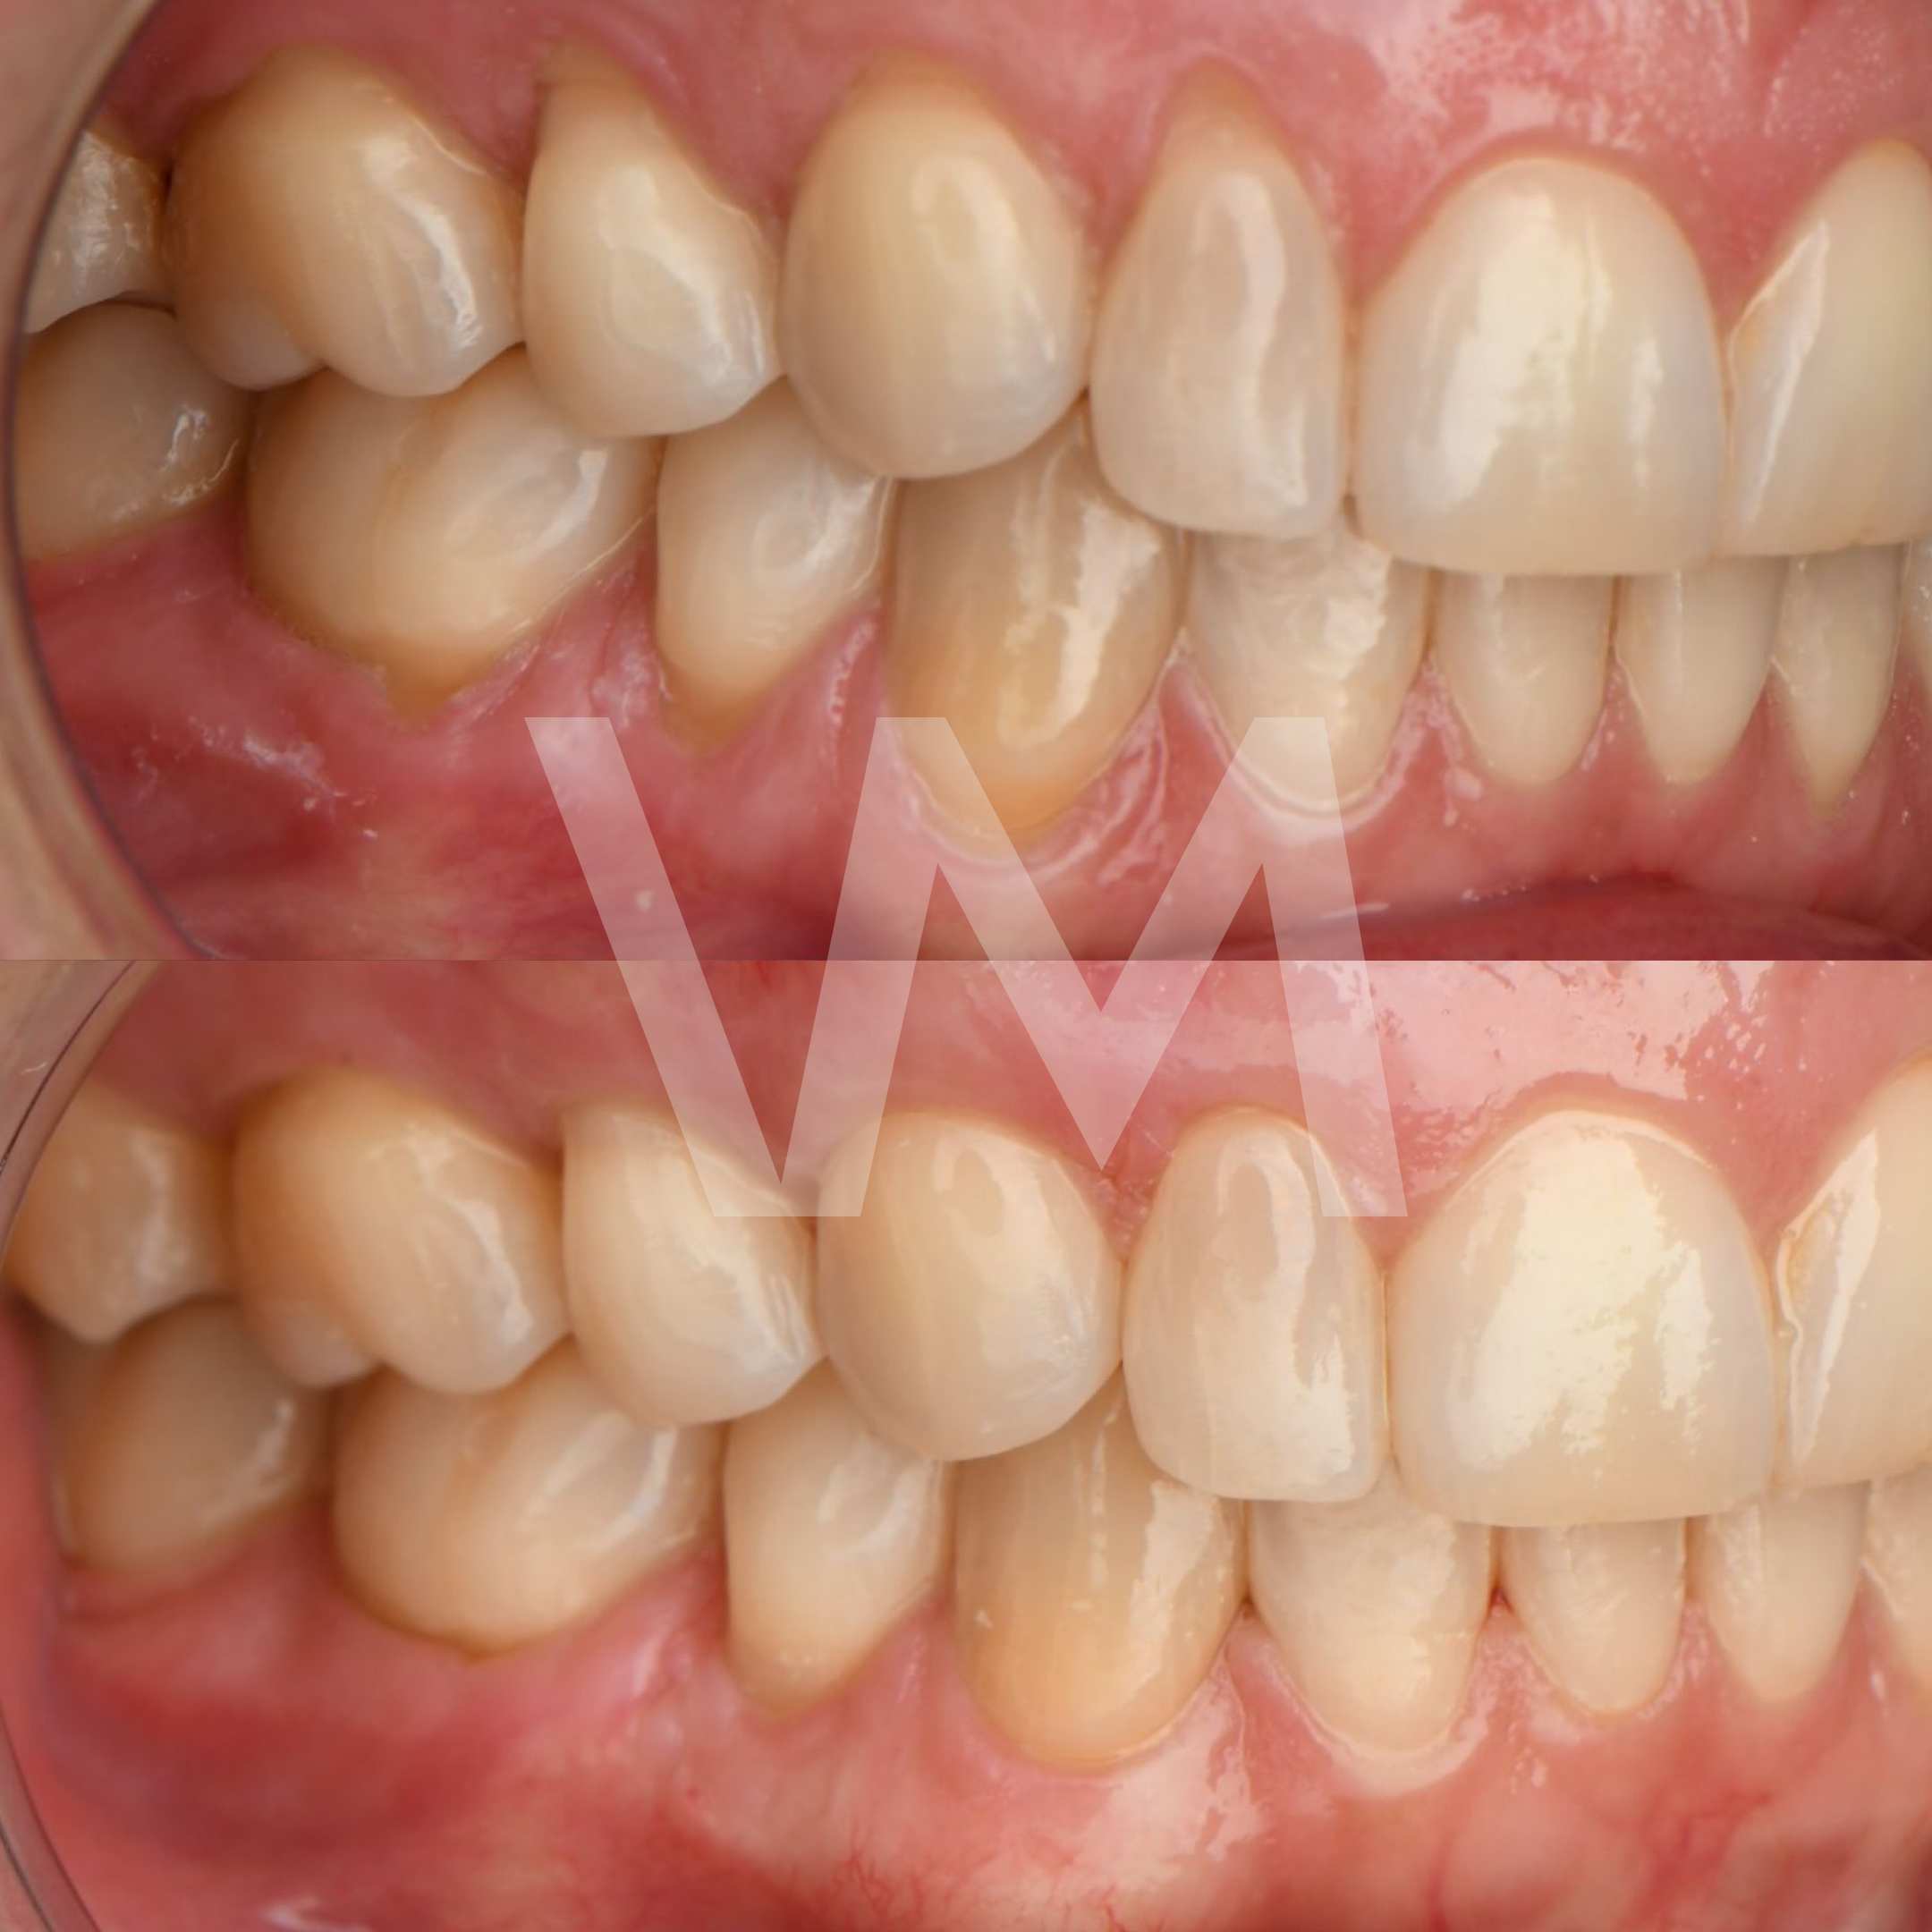

Cirugías de Injertos de Encía del Paladar e Injertos Sintéticos para el Tratamiento de Recesiones Gingivales

Las recesiones gingivales son un problema común en el que las encías retroceden, dejando expuesta la raíz del diente y aumentando el riesgo de sensibilidad dental, deterioro del hueso y pérdida de dientes. Para corregir estas recesiones y restaurar la salud gingival, se pueden realizar cirugías de injertos de encía del paladar e injertos sintéticos.

Casos clínicos realizados por la Dra. Paulina